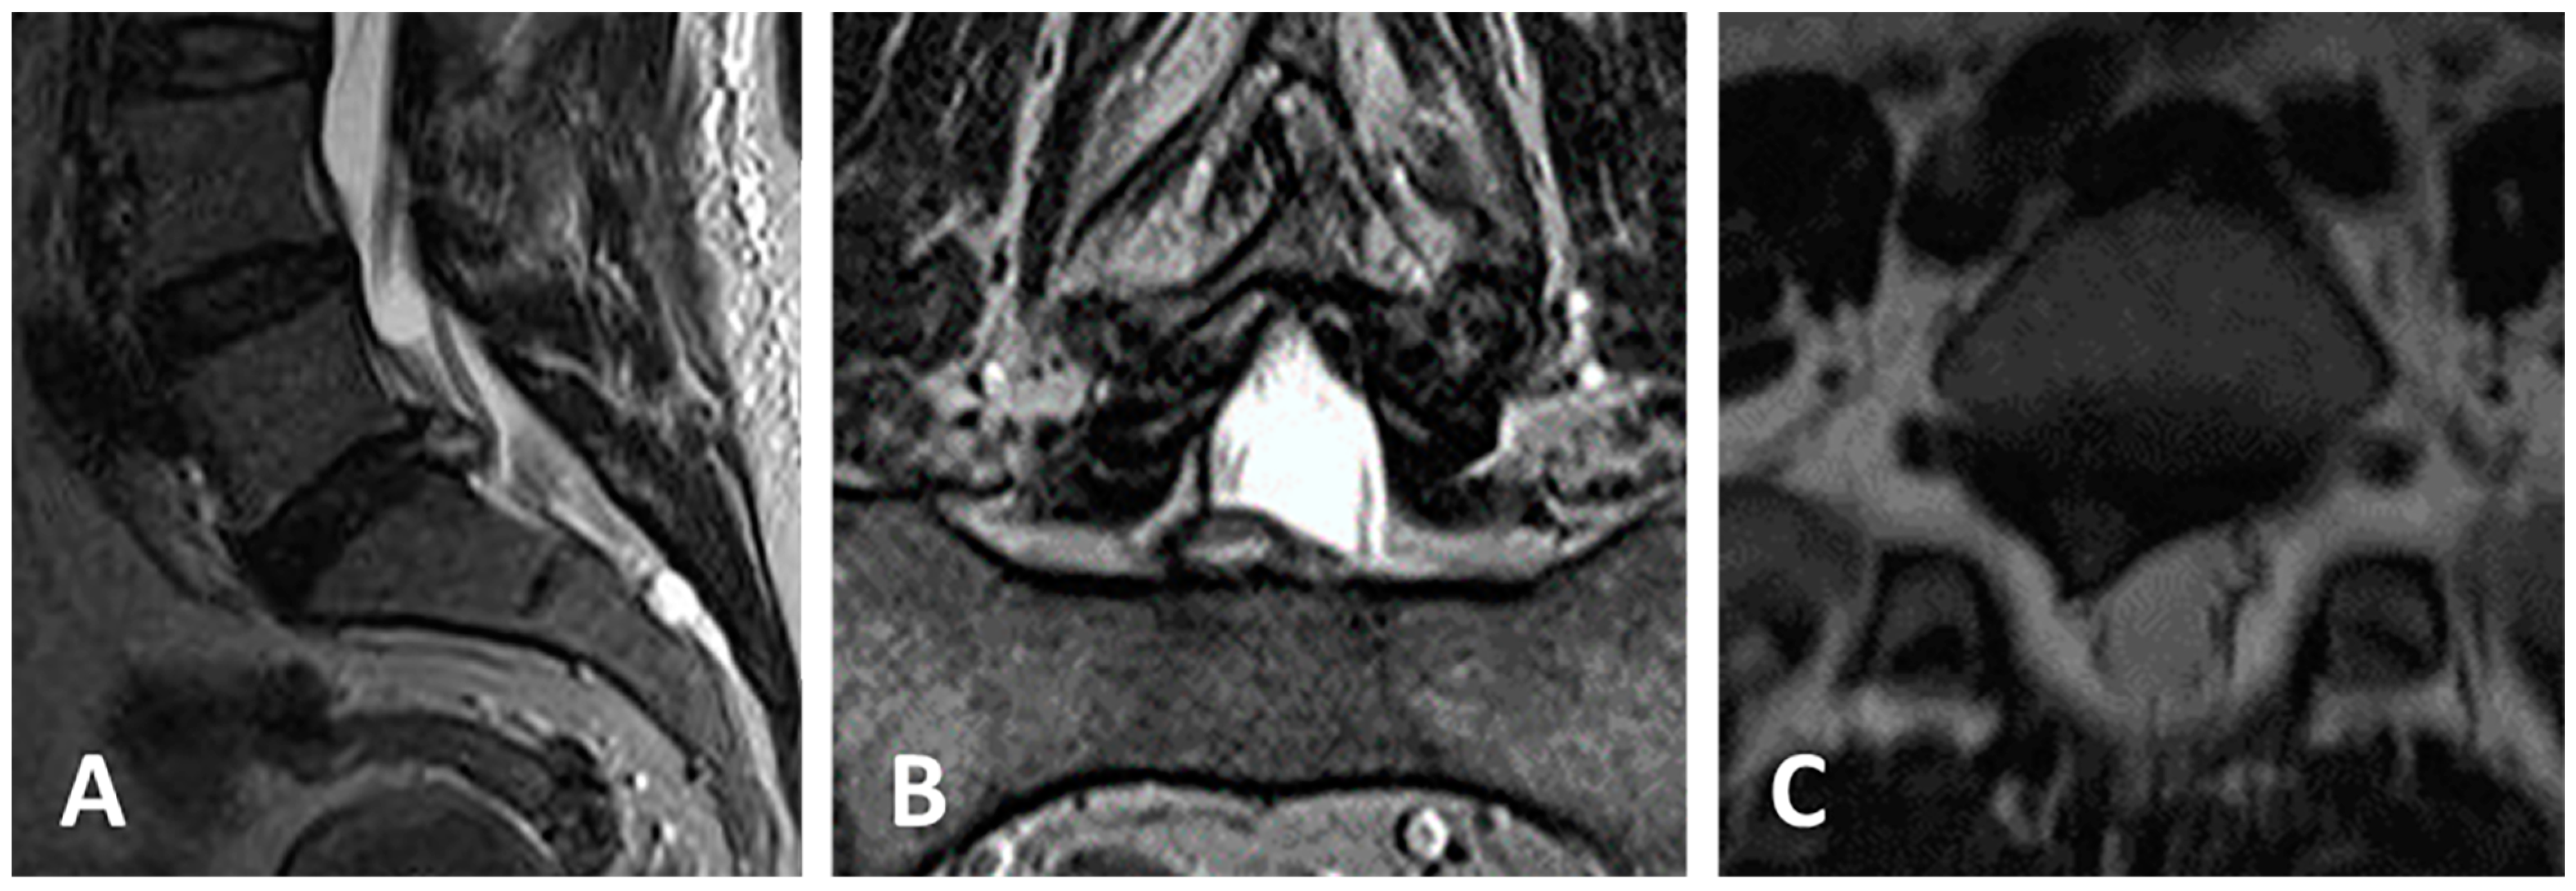

3.3. Clinical Case 1